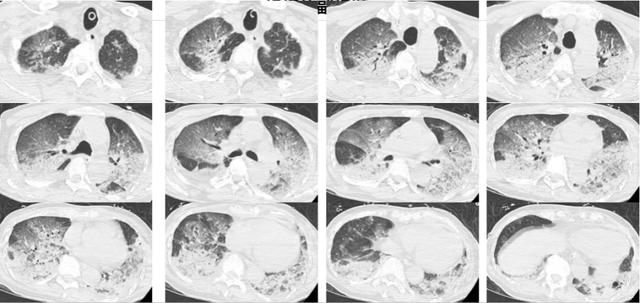

接诊后,韩爷爷意识不清,血压、心率下降,医生们一度怀疑其有肺栓塞或脑梗,于是立即为他进行头颅、胸部CT和肺血管CTA检查。

可结果一出来,医生们吓了一跳,韩爷爷的双肺全白了!

医生检查后排除了他脑中风和肺栓塞的可能,那么,什么病能导致这么大面积的白肺?

经会诊,最终韩爷爷被确诊为热射病诱发的肺水肿。